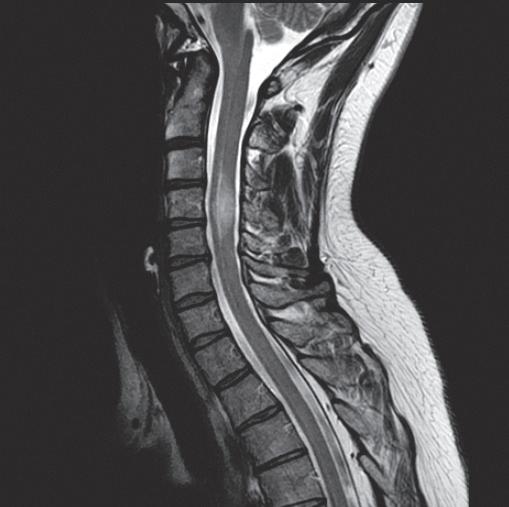

Case Management for Chiropractors: Lumbar & Cervical Herniated Discs

& Headaches

Thursday, November 16 | 8 AM - 5 PM

8 CE DC Location: Green Bay

Instructor: Dr. Steven Yeomans